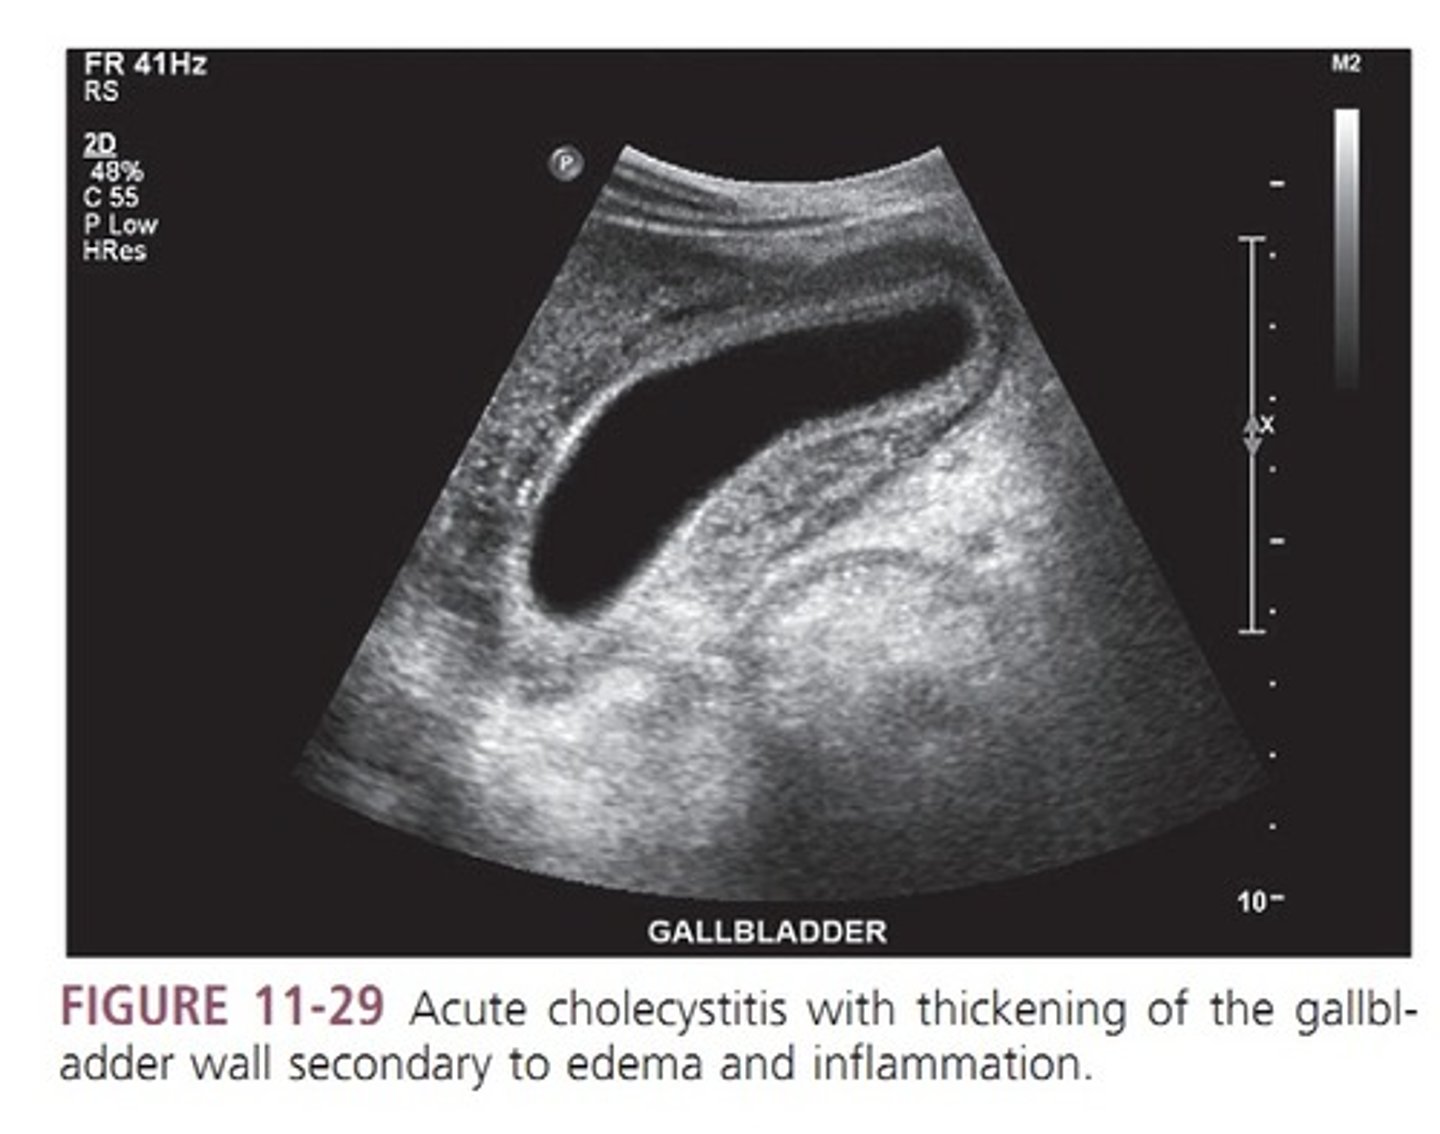

Cholecystitis

inflammation of the gallbladder (can be acute or chronic)

Acute cholecystitis

sudden onset of GB inflammation

acute cholecystitis sonographic findings

- GALLSTONES

- pericholecystic fluid

- sludge

- thickened GB wall

- distended lumen greater than 4cm